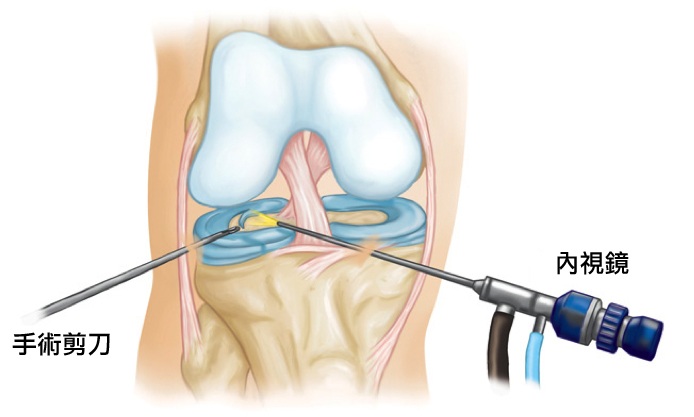

▲「關節鏡手術」示意圖

一開始為了徹底解決膝蓋疼痛的問題,林女士只好接受○○醫院骨科醫師的建議開關節鏡手術,無奈手術後疼痛還是沒有改善,走路仍一跛一跛的。腳一直痛讓林女士每天的心情都非常不好。